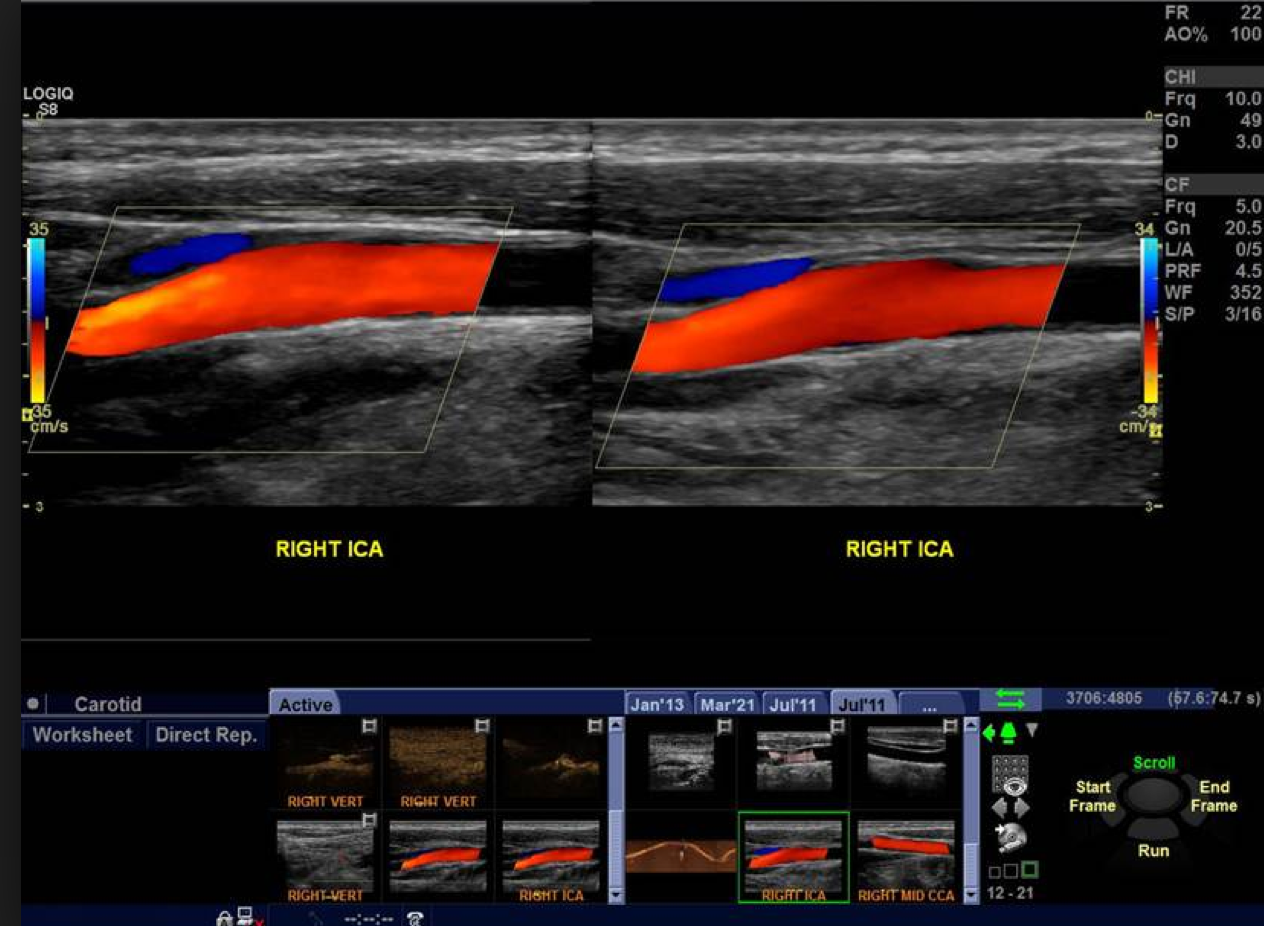

Carotid Doppler Ultrasound

An ultrasound scan is used to assess the arteries in the neck that supply the brain with blood (carotid arteries) for disease that can cause blockage of blood flow to the brain and in turn cause Transient Ischemic Attack (TIA) and stroke.